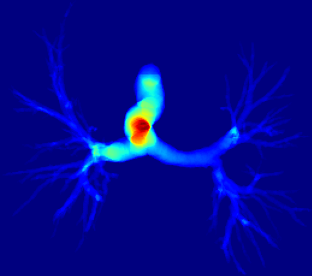

However, current state-of-the-art methods of lung organ segmentation still face several challenges and aspects for improvement. Firstly, the unlimited voxel values, multi-site imaging discrepancy and class imbalance in lung organ images can lead to false-negative and leakage issues in prior segmentation methods, which badly influences the critical early diagnosis of imperceptible lung diseases, e.g., lung fibrosis, nodule and hypertension, etc. Secondly, the presence of numerous slender branches, e.g., bronchioles and arterioles, which are easily lost during the recycled down/up-sampling procedure in Fig. 1, can result in discontinuity, detail loss, and coarse mask predictions. Thirdly, most CNN-based medical segmentation methods treat all points equally during the mask rendering stage, overlooking the vulnerability of border points in Fig. 1 (f) and the importance of explicit border modeling. Lastly, while Vision Transformer (ViT) has shown promise in computer vision tasks [1, 4], its quadratic operation complexity limits its application in 3D high-resolution CT images due to hardware constraints. Meanwhile, most specific datasets for medical image analysis are small and scarce due to laborious manual annotation and privacy protection, which badly restricts the potential of transformer-based top-tier methods.

2.2 Global-Local Cube-tree Fusion

where [0, 1] are the learnable coefficients to balance the importance of each feature; (6) we lastly add the feature to the relative position embedding features (retaining the topology information for inductive bias) for the voxel-wise decoding and refined prediction. Obviously, our proposed global-local cube-tree fusion module focuses merely on all border vulnerable points in Fig. 1(f) rather than all regular dense points in Fig. 1(c), which is more related to the lung organ regions. Experimental results demonstrate the efficacy of this design.